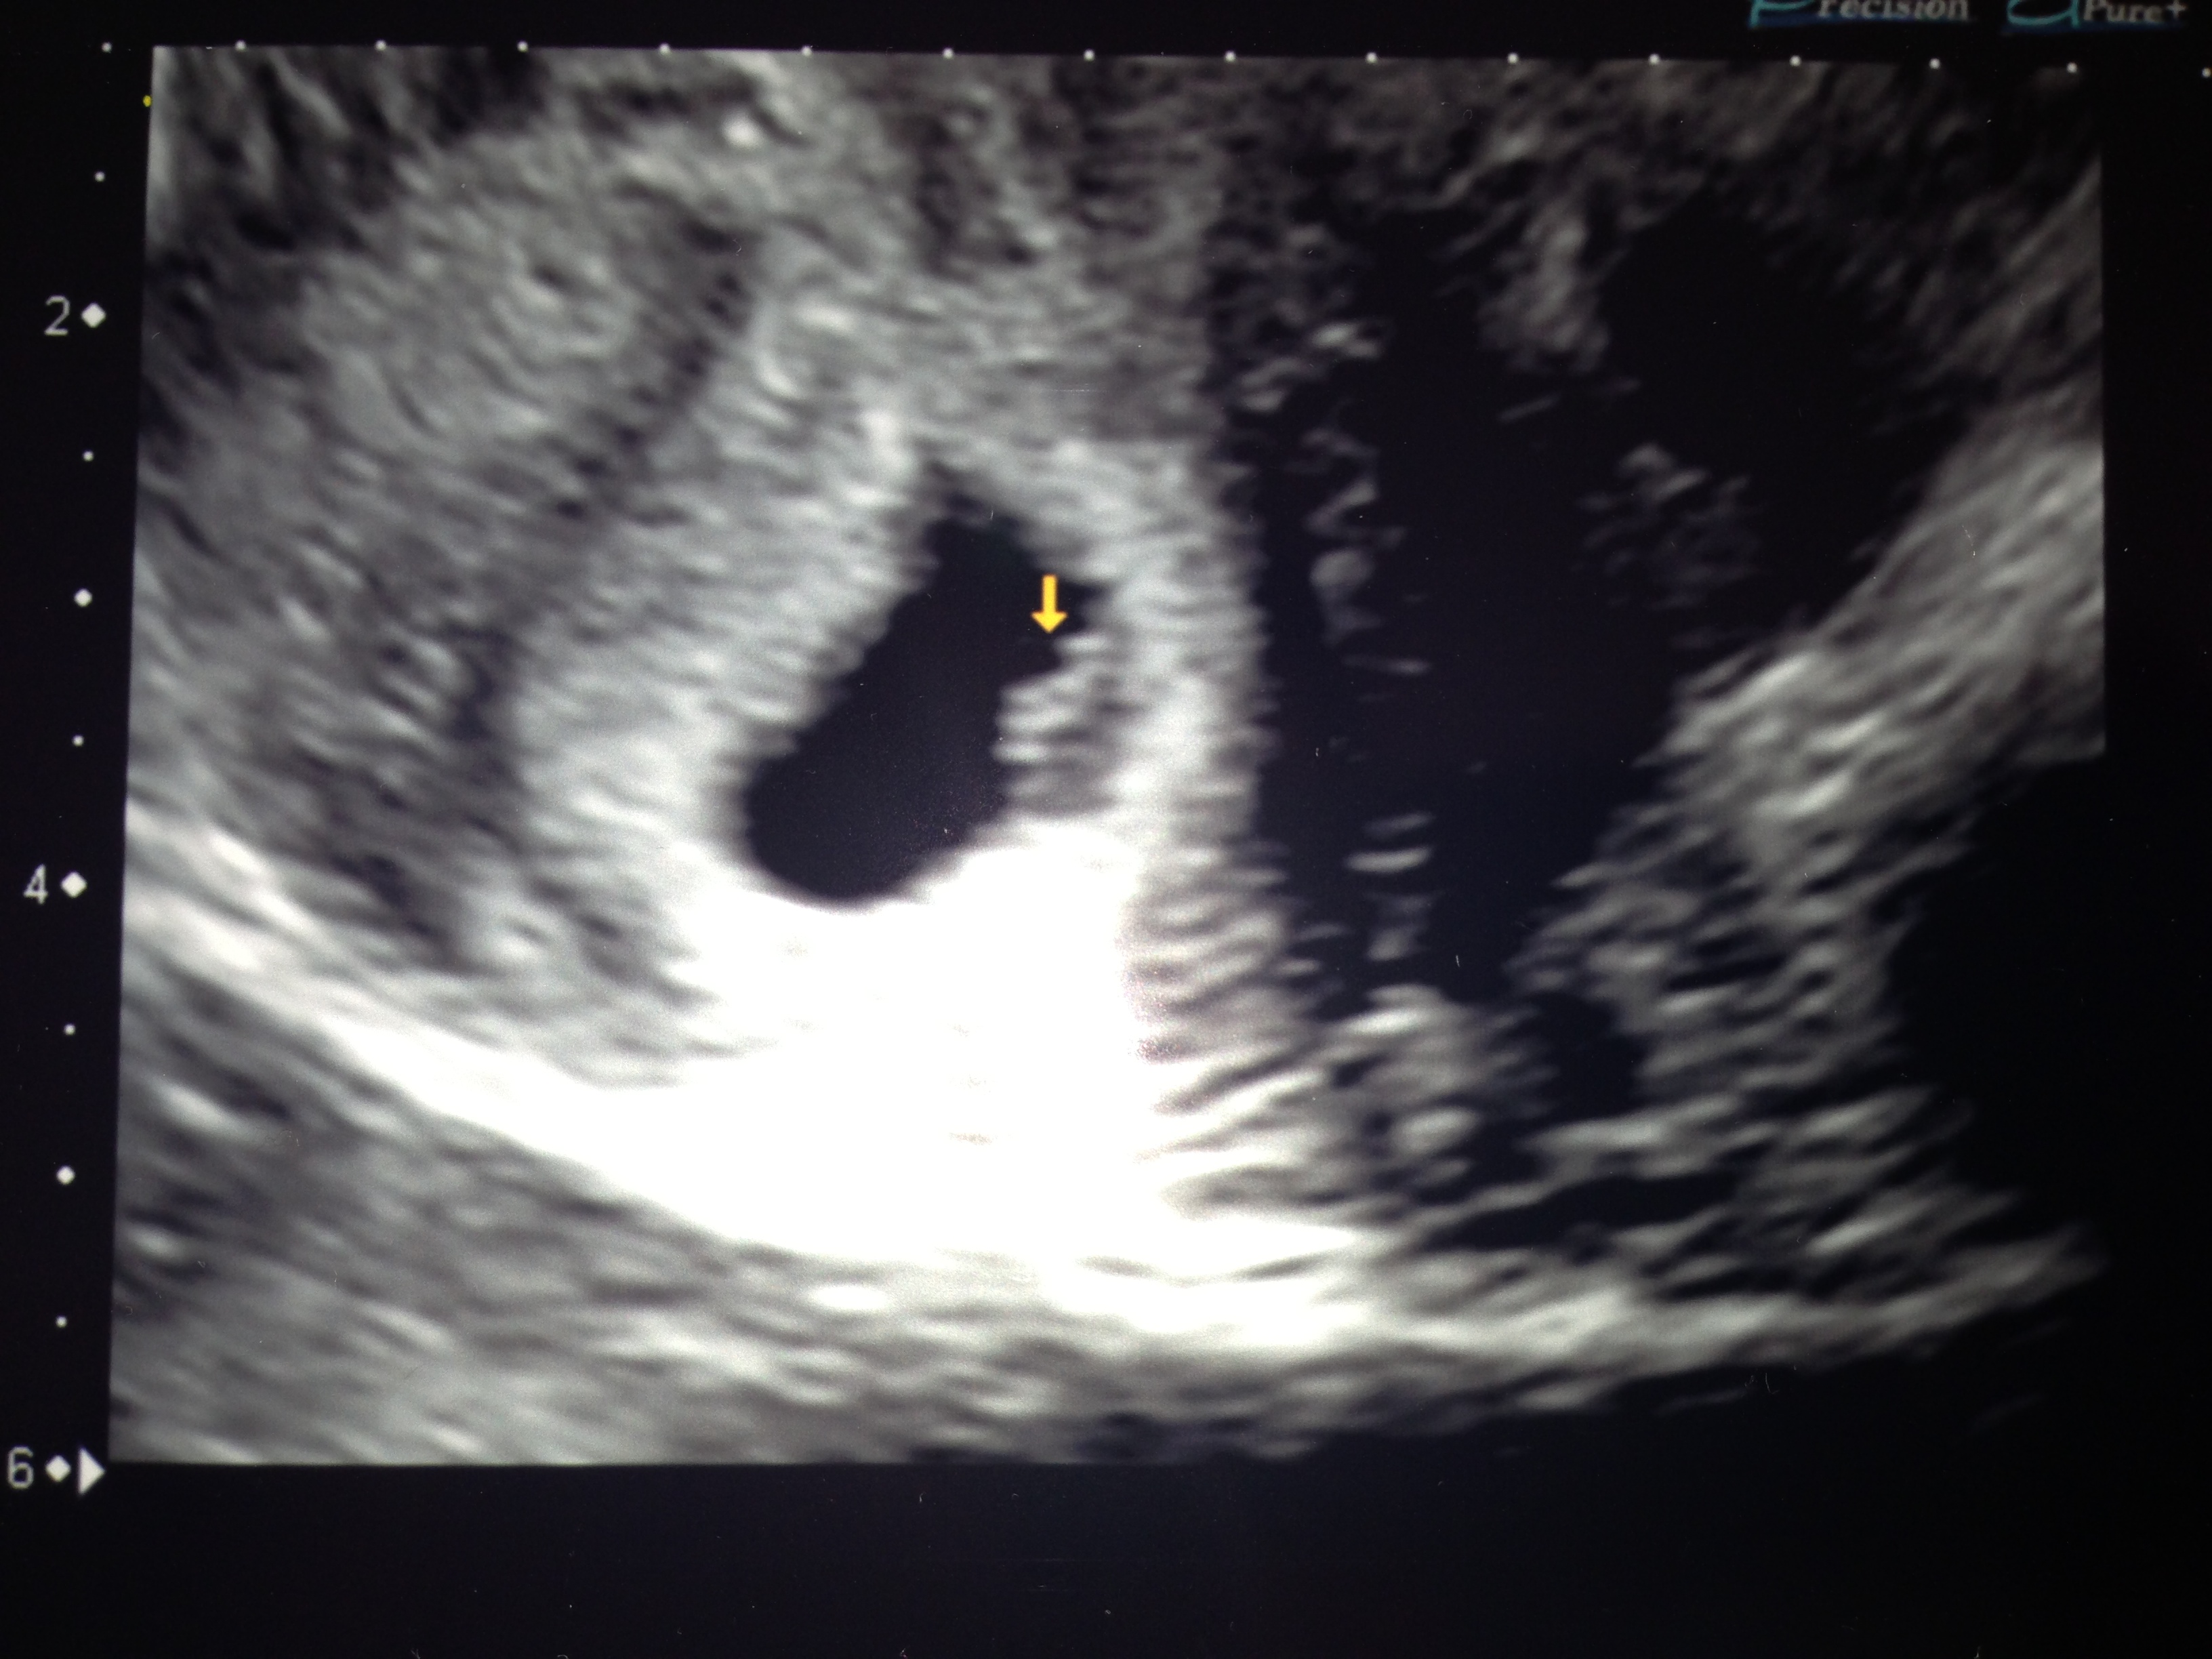

Can I AW this adorable blob?

Just heard back from the midwife about Friday's ultrasound, and everything is where it should be!  They were worried about it being ectopic, but apparently all my pain is from a 6cm fibroid on my uterus...soo, I have a lot of googling to do later.  She said it acts like scar tissue and doesn't stretch like  normal uterine tissue, hence the pain.  But we've got a healthy 6w5d little goober in there, growing away.  Not sure what the heart rate was, but I heard it thumping (okay, flickering) away on Friday.

Isn't this the cutest little blurry blob in the whole world?